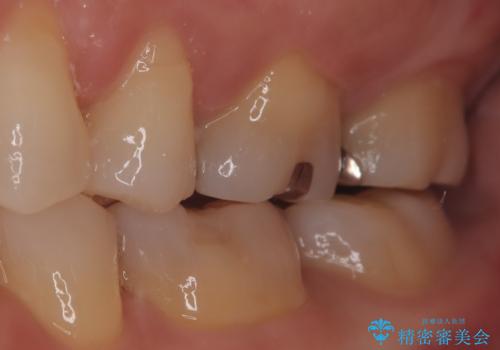

【メタルフリー】セラミックインレーの修復

- メタルフリーを希望された患者さんです。

金属を除去し虫歯の処置をしたあとセラミックインレーにて修復しました。

当院でのセラミックインレーは、ラバーダムを装着してセットしています。